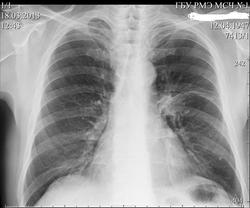

Добавлено изображение( ФЛО-архив). Какая дальнейшая тактика введения данного пациента, при подозрении на центральный рак?

Я рекомендовал выполнить КТ лёгких.К сожалению, не скопировал протокол этого исследования. На словах могу сказать: центральный рак левого лёгкого, гиповентиляция верхней доля.Лимфоаденопатия в области средостения( если не ошибаюсь более выраженая справа).

но не надо торопиься с выводами КТ специалистов. Если рак, то хотелось знать направление роста, экзофитный ? эндофитный? По рентгенограммам можно высказаться о наличии патологического процесса в корне левого легкого. Это прежде всего дополнительная тень в области головки, реакция междолевой щели и межсегментарной перегородки. О гиповентиляции можно судить по сгущению сосудистого рисунка на боковой рентгенограмме (см. рисунок). Наличие обызвествленного первичного комплекса слева, не позволяет исключить реактивацию туберкулеза во внутригрудых имфатических узлах со всеми вытекающими последствиями, отраженными на рентгенограммах. Бронхоскопия необходима в 100%. Вы несколько поторопились коллега Алмо представить данные КТ. Хотелость бы услышать мнения многих врачей. Если будет окончательная морфологическая верификация, напишите.

Томография на левом боку многое разъяснит. Аталектаз 3 сегмента явный в купе с реакцией корня левого лёгкого.

Добавлены протоколы КТ лёгих и бронхоскопии. Вкралась неточность: ещё до проведения флюорографии лёгких пациент предъявлял жалобы на боли слева от грудины, через какое-то время появились жалобы на кровохаркание.Результат гистолоии пока не готов ( в работе).